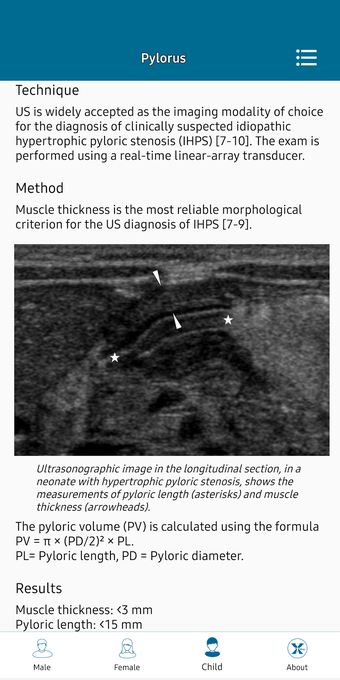

This helpful app is intended for all those who practice medical imaging and for the radiologists who use the application in their work. It is an atlas of the main measurements in radiology and their normal values, divided into six subspecialties: osteoarticular, cervical region, thorax, cardiovascular, abdomen, and pelvis.